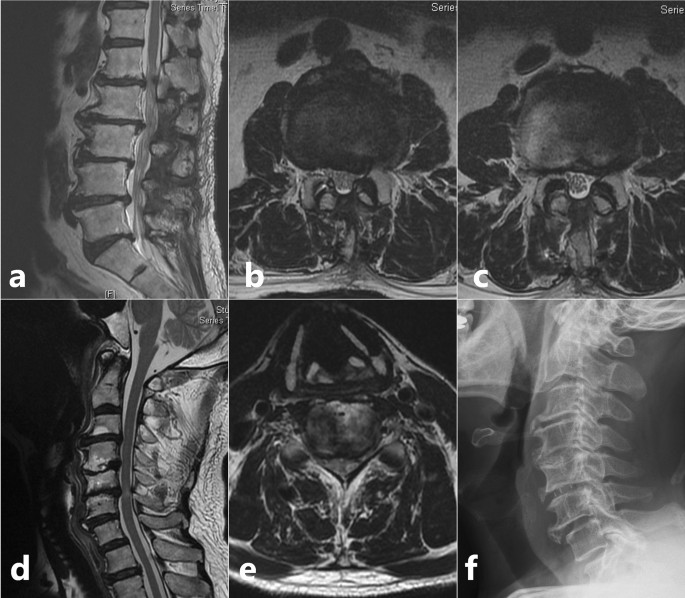

Based on Nurick’s grading of myelopathy, 7 patients (29.2%) were grade 1 showing signs of cord compression but had a normal gait, 5 patients (20.8%) were grade 2 who had gait difficulties but fully employed, 12 patients (50.0%) were grade 3 who had gait difficulties preventing employment, but still walked unassisted. Preoperative JOA score (11.3 ± 1.83) revealed only a minimal compromise in function (33.5%); however, functional assessment using LEFS (pre-operative score = 34.4 ± 7.7) indicated a 57% compromise in lower limb function. Whole spine MRI revealed a cervical level cord compression in all the patients, causing degenerative cervical myelopathy. Among whom, the source of compression was cervical spondylosis in 19 patients. The remaining five patients had cord compression due to OPLL. Eighteen patients (75.0%) had tandem spinal stenosis, with MRI findings of cervical spondylosis coupled with thoracic stenosis and/or lower lumbar stenosis; this includes 3 patients (12.5%) having upper thoracic level cord compression due to OLF or OPLL and 7 patients (29.2%) who had previous lumbar surgery before a mean duration of 5.4 months (Fig. 2).

Scenario of a patient who had previous lumbar surgery but later diagnosed to have category 1 signs and radiologic evidence of a cervical pathology and was grouped under Tandem Spinal Stenosis. (a) Sagittal T2 weighted MRI of lumbar spine showing degenerative spondylosis; (b,c) Axial T2 weighted MRI of L2–L3 and L3–L4 levels showing the previous splitting laminectomy done for decompression; (d) Sagittal T2 weighted MRI of cervical spine showing degenerative spondylosis extending from C3–C6 levels; Stenosis causing signal intensity changes in the cord at C5–C6 level; (e) Axial T2 weighted MRI of C5–C6 level showing apparent stenosis; (f) Post ACDF lateral view X-ray image with PEEK cage at C5–C6 level.

For cervical lesions, anterior cervical discectomy and fusion (ACDF) was performed for 15 patients, Hirabayashi’s laminoplasty for 5 patients with OPLL, combined ACDF and cervical laminectomy for 1 patient and cervical laminectomy for 3 patients. For thoracic stenosis, 4 patients underwent posterior decompression and stabilization (Fig. 3). Among the 18 patients with tandem spinal stenosis, all were treated with staged surgery. The cervical lesion was treated first with procedures listed above in 10 patients while coexisting thoracic or lumbar lesion were treated first in 8 patients. Patients were on rehabilitation and rest for a period of 6 weeks. After which, they were allowed to carry on with household activities. Four of those patients with tandem spinal stenosis developed radiculopathy and objective lower limb weakness pertaining to the course of a particular nerve after a mean duration of 7.2 ± 1.5 months, which required decompression, interbody fusion and stabilization of the lumbar spine.